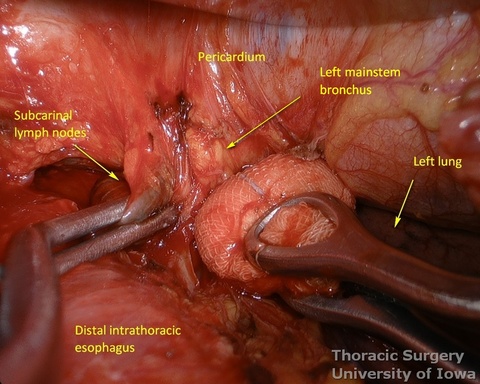

- Esophagus is circumferentially mobilized under direct vision using combination of sharp and blunt dissection up to the level of the carina.

- Esophageal arteries (aorto-esophageal branches) and vagal nerves are divided under direct vision using the energy device.

- Periesophageal and subcarinal lymph nodes are dissected separately or en-block with the esophagus under direct vision.

- Dissection of the distal and mid esophagus is completed using a combination of an energy device and suction tips.

- Through the abdomen, the hiatus is enlarged to allow a hand entry. Circumferential midesophageal and proximal esophageal dissection is gently completed in the superior mediastinum with fingers sequentially through the neck incision (along with gently traction on the cervical esophagus) and hiatus (along with gently traction on the Penrose around the gastroesophageal junction).

- The transhiatal retractor is reinserted, if needed, to divide remaining adhesions under the direct vision and to assure hemostasis.